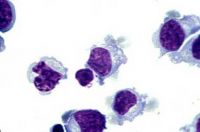

Makrofág

Makrofág.

Vliv ionizujícího záření do dávky 10 Gy nenarušuje životnost makrofágů. Ještě 24 hodin po dávce 115 Gy je 50 % buněk živých. Radiorezistentní je i proliferace a migrace makrofágů. Podobně jako makrofágy reagují na ionizující záření i dendritické buňky (snížená životnost, prezentace antigenu), které jsou významnými pomocnými buňkami imunitního systému.